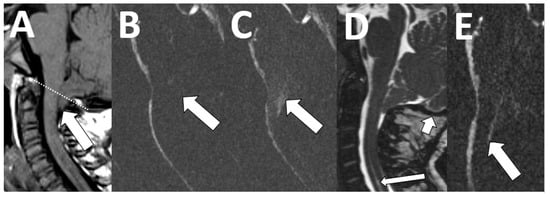

Our contextualized MRI cervical spine protocol for the CCJ includes sagittal T1-weighted images to assess for the presence of diagnostic anatomical features of Chiari I deformity, as well as a 3D heavily T2-weighted sagittal sequence to evaluate restriction of the CSF spaces at the CCJ. We also include a PC CSF flow study, which allows additional evaluation of CSF flow dynamics and abnormal motion of intraspinal contents (Figure 7).

Figure 7. Chiari deformity. An 18-month-old female with new onset seizures and speech delay. Sagittal T1-weighted image shows descent of the cerebellar tonsils ((A), arrow) below the foramen magnum ((A), dotted line) by 8 mm. There was diminished flow across the posterior craniocervical junction ((B), arrow) and abnormal motion of the tonsils ((C), arrow). Follow-up imaging at 4 years of age shows interval suboccipital decompression surgery ((D), short arrow) and improved CSF flow across the craniocervical junction ((E), arrow), as well as resolved abnormal tonsillar motion. A small cervical syrinx persists post-surgically ((D), long arrow).